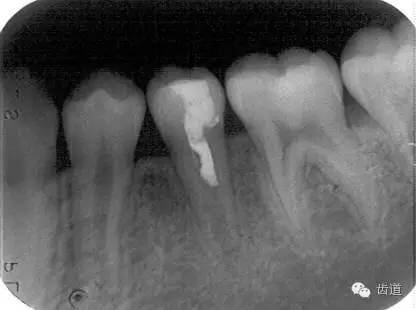

Apexification

Apexogenesis

術(shù)后三個月

術(shù)后六個月

術(shù)后兩年